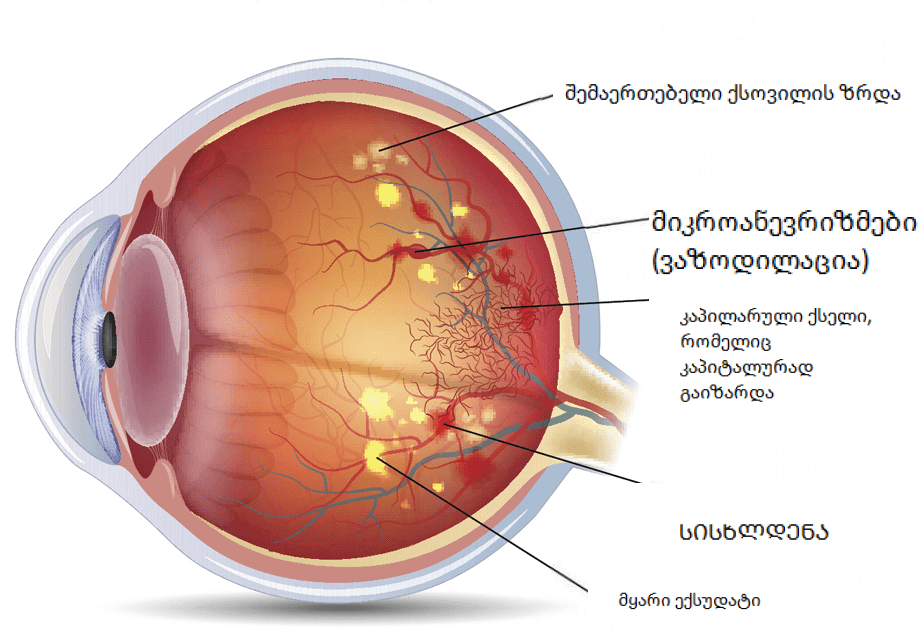

ინტერნეტიდან: ბადურის დისტროფია, არსებითად, არ არის ცალკეული დაავადება, არამედ დაავადებათა მთელი კომპლექსი, რომელიც ასე თუ ისე წარმოდგენილია ბადურის დეგენერაციული დაზიანებით ან მისი განუვითარებლობით. ჩვეულებრივ ვითარდება ასაკთან ერთად, რაც იწვევს თვალის ლინზის კატარაქტს და სრულ სიბრმავეს.

სამწუხაროდ, ბევრი ვერ ხვდება, რომ სხვადასხვა წვეთების გამოყენება მყისიერი შედეგისთვის, ისინი მხოლოდ აუარესებენ თვალებს. და ზოგიერთი ადამიანი საერთოდ არ აქცევს ყურადღებას სიმპტომებს, მათ მიაჩნიათ, რომ ეს საკმარისია მხოლოდ თვალების გასაწმენდად ან გასატარებლად და ყველაფერი გაივლის. მაგრამ ეს არ ართმევს ადამიანს პათოლოგიას! ბადურა გააგრძელებს დაშლას და მხედველობა სტაბილურად დაეცემა.

ყველა ეს დაავადება თვალის სისხლძარღვების დარღვევის შედეგია. მაგრამ ადამიანების უმეტესობა აგრძელებს ტანჯვას და იყენებს უსარგებლო წვეთებს ან ტაბლეტებს, სიმპტომების აღმოფხვრის იმედით.